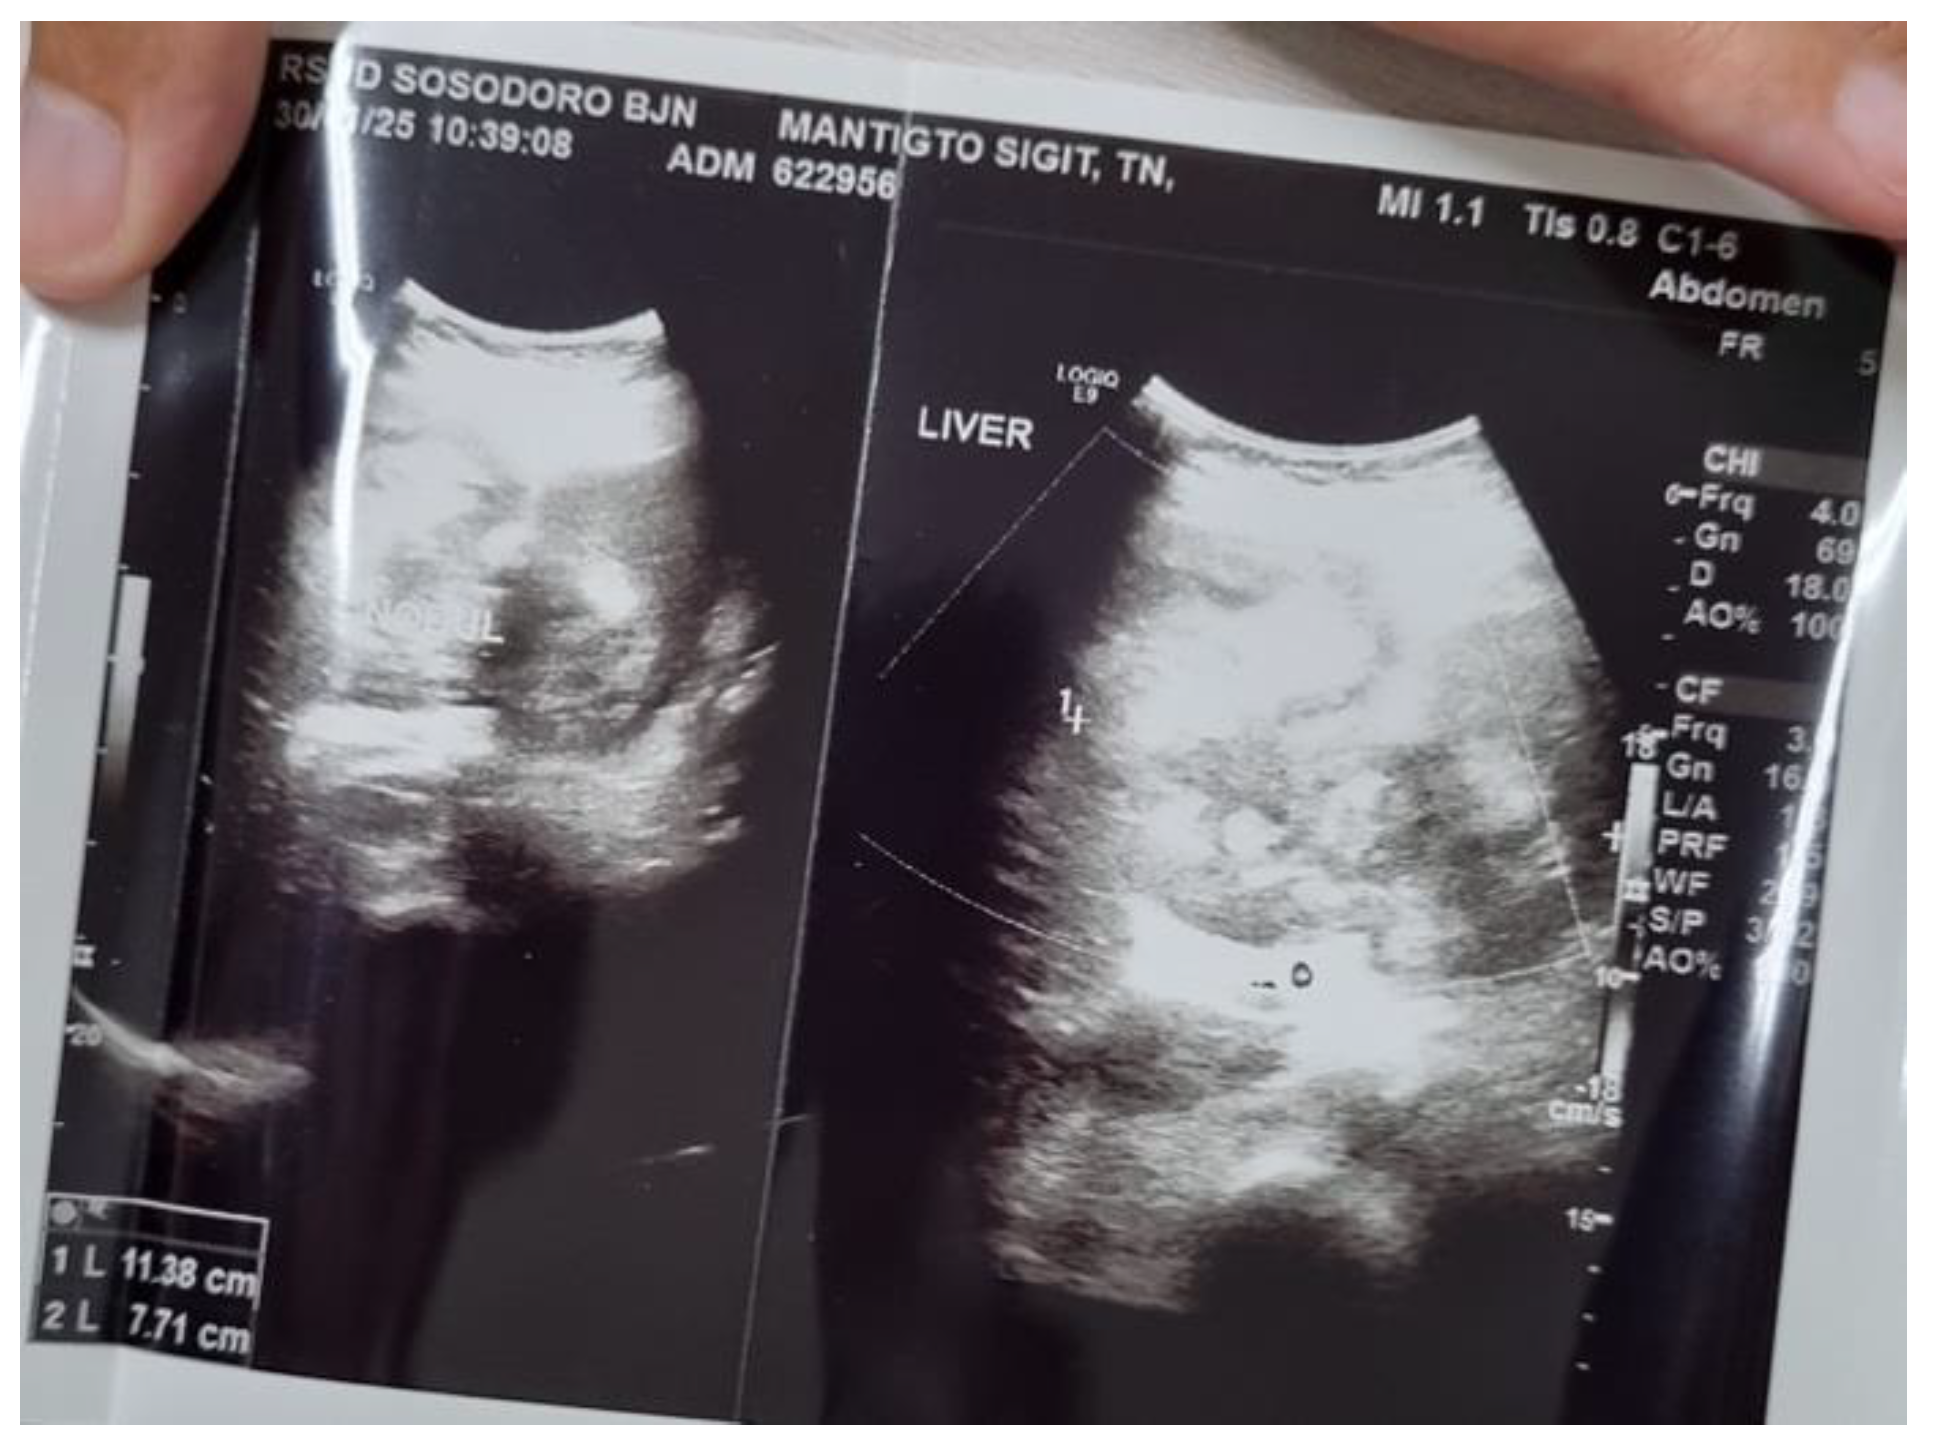

Background: Liver abscesses represent an atypical yet potentially life-threatening complication of bacterial, fungal, protozoal, and helminthic infections. Frequently, the clinical findings associated with liver abscesses are nonspecific, necessitating a reliance on imaging for diagnosis. It is uncommon for a liver abscess to radiographically resemble a malignant liver tumor such as hepatocellular carcinoma (HCC). Here, we present the case of a 45-year-old male who was initially diagnosed with HCC (BCLC C) but was subse-quently found to have a liver abscess following biopsy. Case Presentation: A male patient, 45, presented with stiffness and pain in the right upper abdomen. He complained of nausea and vomiting since 10 days before admission as well. All supportive imaging suggested a diagnosis of HCC. A liver abscess was detected during a biopsy. A liver ultrasound-guided FNAB showcased chronic, suppurative in-flammation with negative acid-fast bacilli on Ziehl-Neelsen staining. The patient sub-sequently developed a complication of middle hepatic artery bleeding and underwent immediate embolization. Discussion: In fact, a liver abscess can be the initial manifestation of HCC. Patients tend to have a poorer prognosis because the diagnosis of a liver abscess often delays the discovery of the underlying HCC. Radiographically, liver abscesses range from well-circumscribed cystic lesions with an enhancing rim to heterogeneously enhancing mass-like lesions, which are sometimes indistinguishable from liver neoplasms. However, it is so scarce that a liver abscess may radiographically mimic HCC. Conclusion: Assessing liver abscess is somewhat complicated since the symptoms vary a lot. Therefore, a correct and exact diagnosis entail a combination of more comprehensive clinical and supporting examinations.